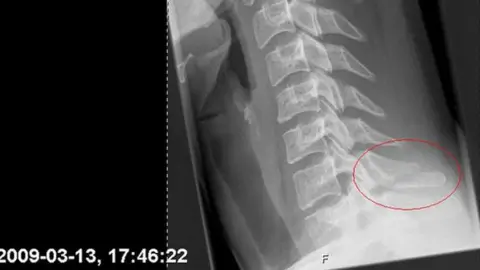

While racing down the slopes of a Swedish ski resort in 2009, she fell and broke her neck.

"I was trying to get up, but I'm like, 'Oh, I can't move my arms.' And that's when I realised it was a bit more serious.

"The doctor said that I was one millimetre from the nerve getting cut off," she recalls. "They were like, 'This was really, really lucky.'"